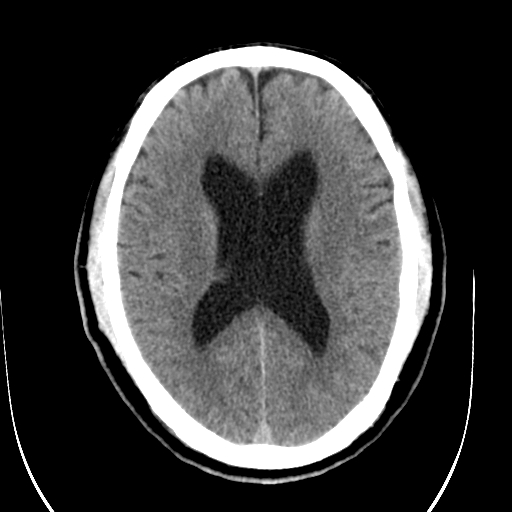

标题: CT28335:男,58岁,请各位看看是不是有脑积水,蝶窦内高密 [打印本页]

标题: CT28335:男,58岁,请各位看看是不是有脑积水,蝶窦内高密

轻度积水,蝶窦正常。

脑积水!建议行mri!

1)脑积水。2)副鼻窦炎。